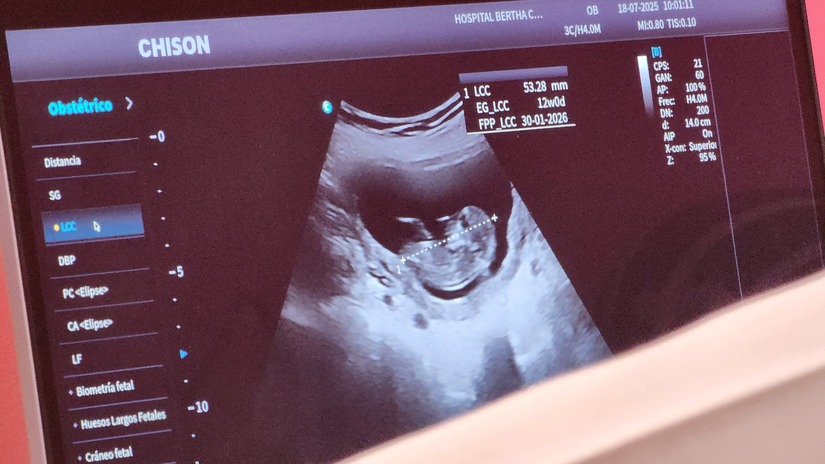

“Realizamos lo que es la feria integral de salud a las mujeres. Específicamente embarazadas entre las 11 y las 13 semanas de gestación. Se realiza lo que es una evaluación de lo que es el embarazo”, destacó.

“Este ultrasonido consiste en tomar lo que es la longitud del bebé para determinar inicialmente la edad gestacional. Posteriormente se hacen las mediciones de algunos marcadores que nos orientan a ver qué tipo de malformaciones puede tener este bebé o qué tipo de problemas puede tener”, explicó.

Estos exámenes, indicó, permiten también hacer diagnóstico en las madres para prevenir preeclampsia de inicio temprano, principal causa de complicaciones a las embarazadas y sus bebés.